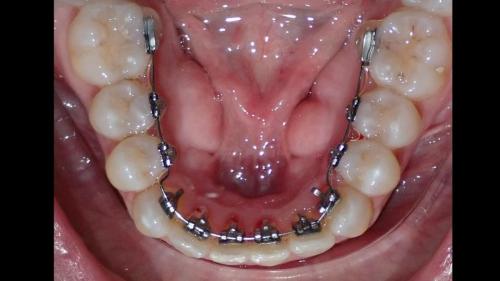

Galería de Sonrisas

large-Ortodoncia Lingual

large-Ortodoncia lingual invisible

large-Lingual